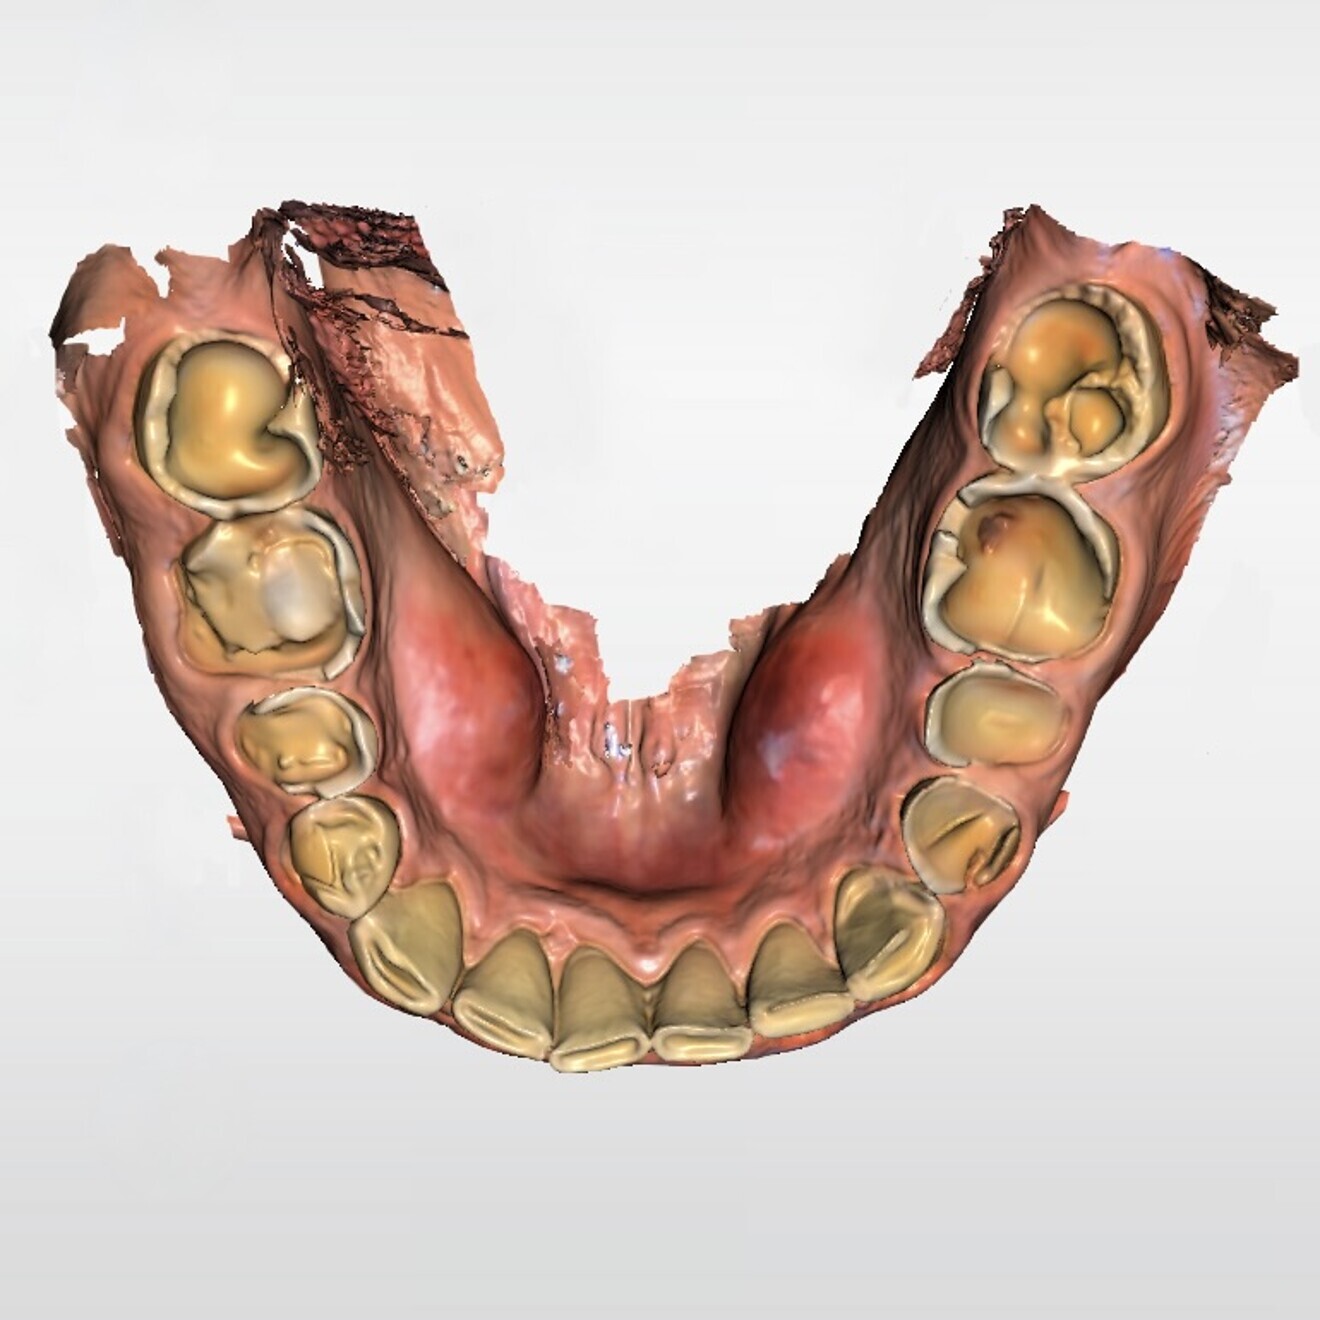

Fig. 3b: Digital scan of the initial situation. Lower jaw.